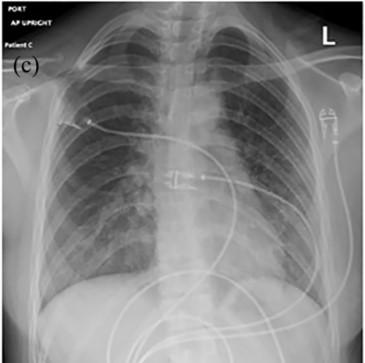

image: Chest X-ray image of patient with lung injury due to vaping

There are many similarities between EVALI and COVID-19 symptoms, laboratory results and radiologic findings. Common symptoms include fever, cough, nausea, abdominal pain and diarrhea. Both conditions also show bilateral ground glass opacities in chest imaging.

With the COVID-19 pandemic, it is easy to miss EVALI diagnosis. The patients in the case series showed up with fever, nausea and cough. They had fast heart rate, rapid breathing and low oxygen levels in their blood. Their laboratory results pointed to inflammation commonly seen in COVID-19, with higher white blood cells (WBC) count and elevated inflammation. Their chest imaging revealed non-specific ground glass opacities. While everything indicated COVID-19 infection, their SARS-CoV-2 testing returned negative.